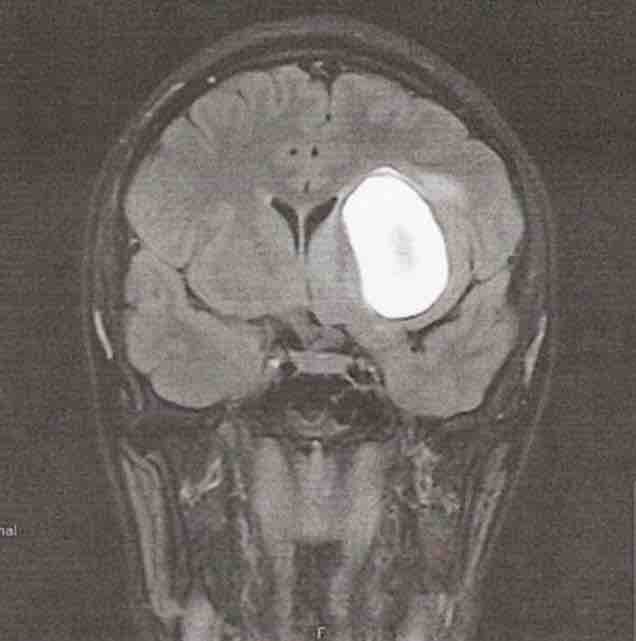

When I was just 14 years old, I suffered a stroke caused by an arteriovenous malformation (AVM) (pictured on the left). Overnight, my childhood changed. I had to relearn parts of life that others take for granted. My strength, my confidence, and my future all suddenly felt uncertain.